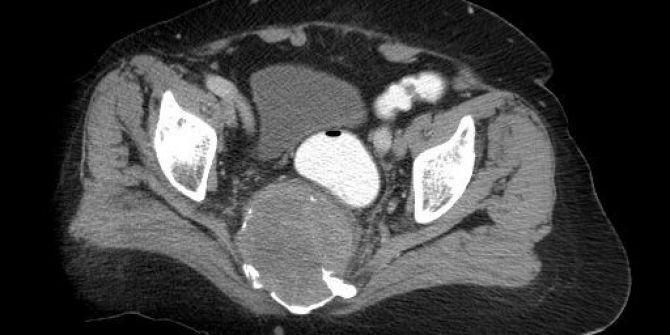

Bel Fıtığı Şikayetiyle Gittiği Hastanede Oturak Kemiğinde 10 Santimetrelik Tümör Çıktı